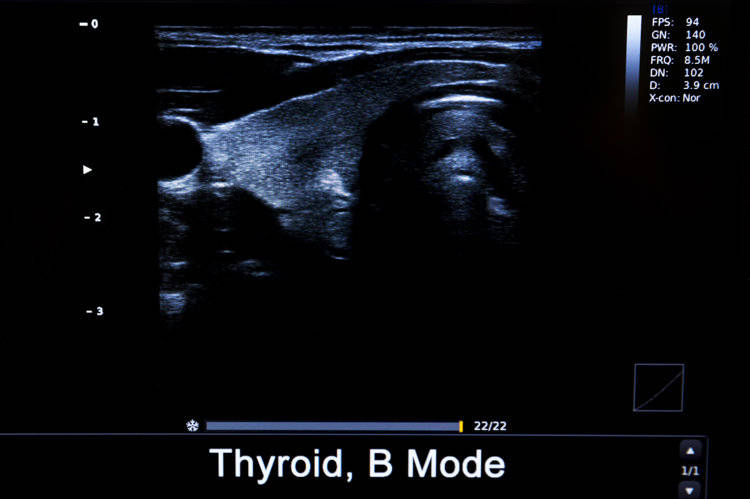

• 甲状腺结节

甲状腺结节是指甲状腺组织内出现的局限性肿块,会随着吞咽动作上下移动。

中国医学科学院肿瘤医院山西医院头颈外科主任李德志表示,B超检查中有20~30%的人会检出大小不一的甲状腺结节,大部分为良性,最终诊断为恶性的概率仅有3~4%。但还是建议普通人每年进行一次甲状腺检查。

在发现结节后,要及时找一位专业的医生判断良恶性,之后再遵医嘱是进行治疗还是随访。